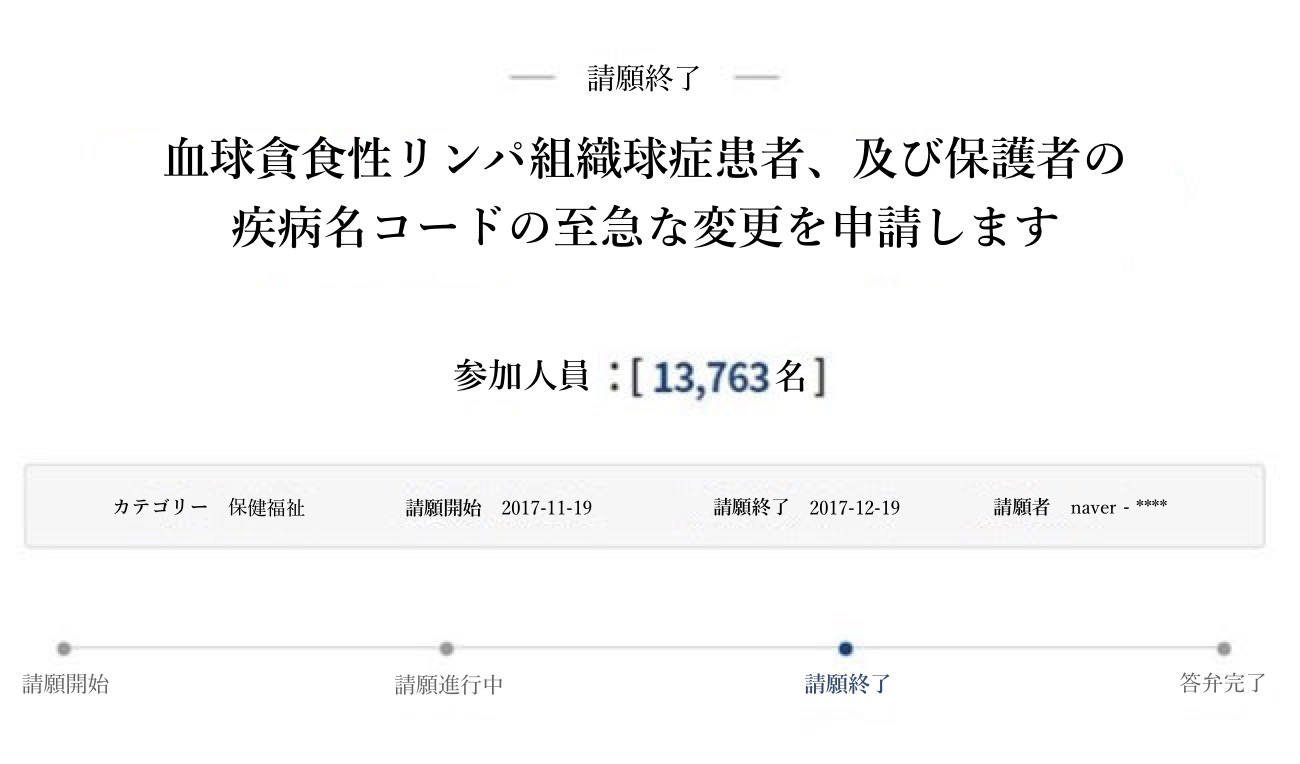

抗がん治療が切実な病気ですが、癌とはその疾病コードが異なるため、ナヨンちゃんとその家族は保険料を受け取ることができなかったそうです。お母さんは、この病気と関連して、大統領官邸宛に「国民請願」を揚げたこともあります。

その請願の内容は、「血球貪食性リンパ組織球症」の疾病コードを変えてほしいという趣旨の文章でした。

しかし、この請願は、当時はあまり公論化されず、残念ながら国民からあまり注目されなかったそうです。